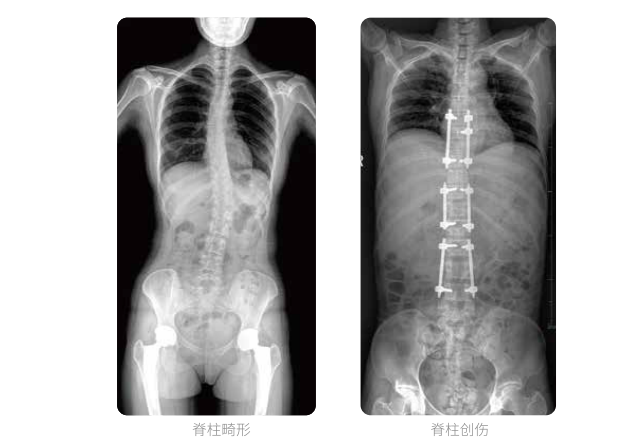

大視野不拼接 一次曝光覆蓋全脊柱

全脊柱臨床影像

PLX8600大視野平板動(dòng)態(tài)DR全脊柱一次成像攝片適用于兒童、成人、老年人腰椎退行性病變、強(qiáng)直性脊柱炎、脊柱結(jié)核等臨床應(yīng)用,在此類大視野的臨床拍攝中發(fā)揮了極大的價(jià)值。

PLX8600大視野平板動(dòng)態(tài)DR可在透視情況下多角度觀察病灶部位,做術(shù)前診斷及術(shù)后愈合的檢查,如脊柱斜位透視,可觀察椎弓根峽部,診斷椎體是否滑脫等情況;可在脊柱運(yùn)動(dòng)狀態(tài)下通過透視模式觀察全脊柱狀態(tài),了解病變處脊柱的活動(dòng)度及骨結(jié)構(gòu)的關(guān)系,配合點(diǎn)片功能快速獲得高清的關(guān)鍵幀影像,輔助醫(yī)生制定更準(zhǔn)確的手術(shù)方案。